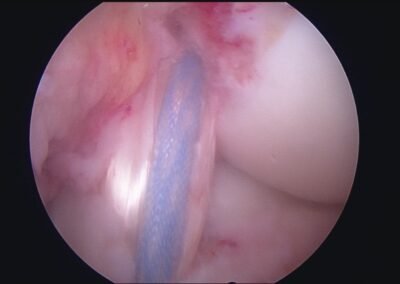

GalleryShoulder rotator cuff repair Meniscus root repair Meniscus repair Bankart repair for recurrent shoulder dislocation ACL reconstruction Machines Instruments